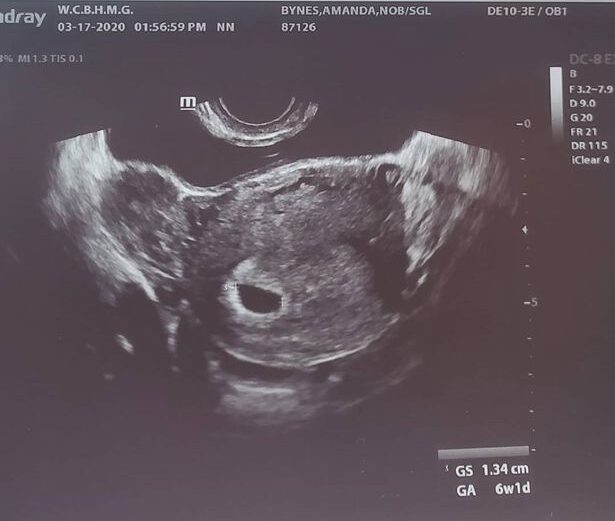

Two months ago Amanda Bynes publicly shared on Instagram an ultrasound photo claiming that she’s pregnant.

Amanda had shared her ultrasound photo on March 17th, with the caption “Baby on board” just days after she and Paul reconciled. It was left unclear whether Amanda lost the baby or if she was never pregnant in the first place.